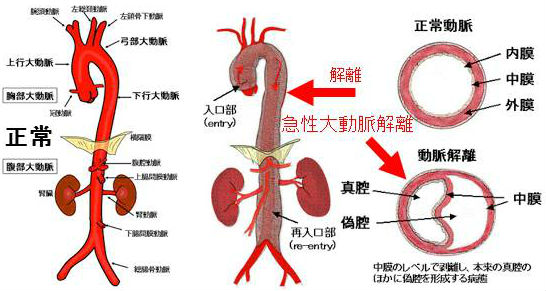

甲状腺機能低下症/潜在性甲状腺機能低下症/橋本病で動脈硬化が進行、急性大動脈解離とDIC・心タンポナーデ、腹部大動脈瘤、甲状腺動脈瘤破裂おこる。急性大動脈解離は血中Dダイマー上昇。A型上行大動脈解離が大動脈基部に及ぶと心臓栄養する冠状動脈入口部を圧迫、急性心筋梗塞と同じ心電図所見に。B型解離(DeBakey III)で主要分枝を含まない領域に限局は降圧治療のみ。甲状腺動脈瘤は血栓塞栓症なく、高率に破裂し死亡率20%のため無症候性でもコイル塞栓術、外科的切除。動脈硬化進行してできる腹部大動脈瘤は破裂すると突然死。通常、無症状で破裂始まると腹痛・腰痛。

動脈硬化が原因でおこる急性大動脈解離、腹部大動脈瘤、甲状腺動脈瘤を以下に解説します。

急性大動脈解離とは、大動脈壁の脆弱さ、動脈硬化、高血圧などが原因で、血管内膜に亀裂が入り、中膜が裂け、内腔側が内膜フラップ(intimal flap)になって、その下に偽腔が生じる病態です。